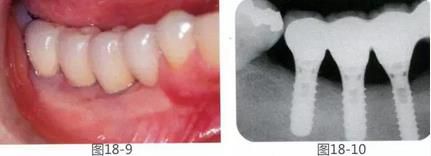

360截圖20170422142137538.jpg

圖18-9,10  GBR修復(fù)后10年。